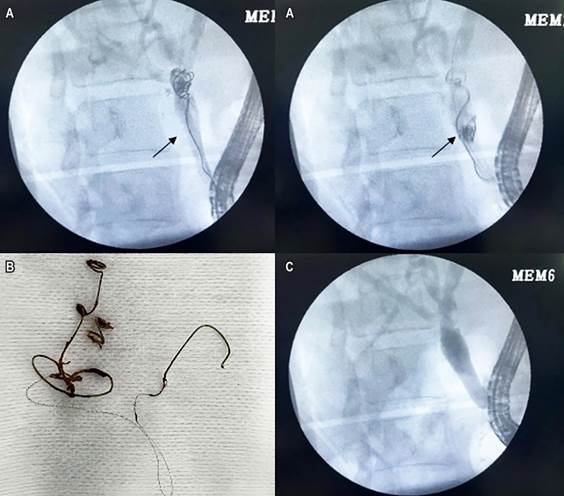

This is a 54-year-old female patient who underwent laparoscopic cholecystectomy in 2022, resulting in bile duct injury and a biliary fistula. Postoperatively, she required ERCP and stent insertion, as well as management of haemobilia with hemodynamic repercussions secondary to a pseudoaneurysm of the right hepatic artery, which required emergency embolization with coils. She was admitted to the gastroenterology service for a scheduled ERCP and biliary stent removal eight months after the initial procedure. Fluoroscopic imaging revealed a linear foreign body within the biliary tract, which was successfully extracted using a Dormia basket (coils) (Figure 3).